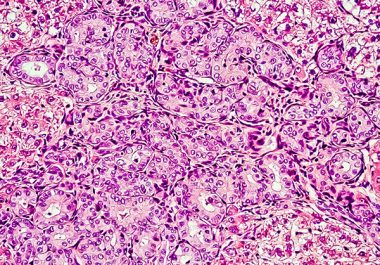

The FDA has granted accelerated approval to a molecularly targeted therapeutic along with a companion diagnostic to treat certain patients with cholangiocarcinoma. The U.S. Food and Drug Administration (FDA) has granted accelerated approval to...

The first molecularly targeted therapeutic for use in the treatment of bile duct cancer has been approved by the FDA.